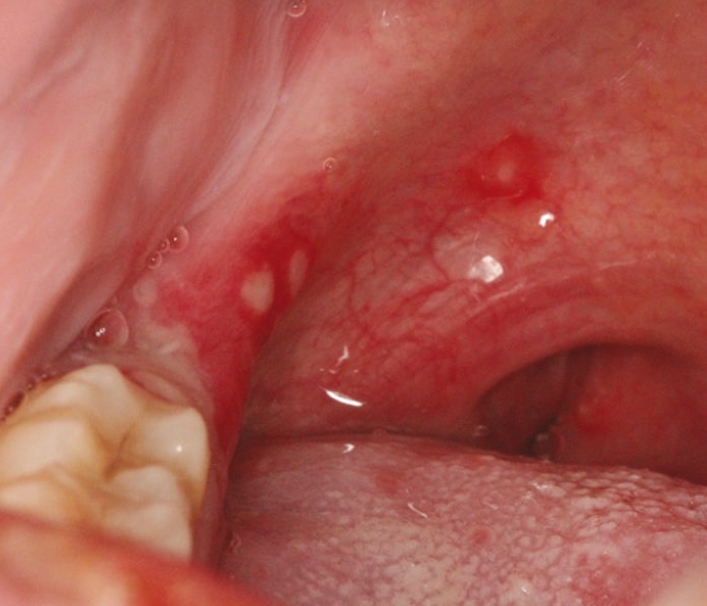

主要症状是口、手、足、臀部(有时还包括生殖器)出现溃疡,外观为小的红斑、凸起或水疱。口中的溃疡会导致吞咽疼痛。手和足的溃疡也可能引起疼痛。患者可能仅在部分区域出现溃疡。并非所有患者都会在手、足和口发生溃疡。疱疹性咽峡炎也可导致咽部溃疡。手足口病有时会导致发热,而疱疹性咽峡炎患者一般会突然出现高热。